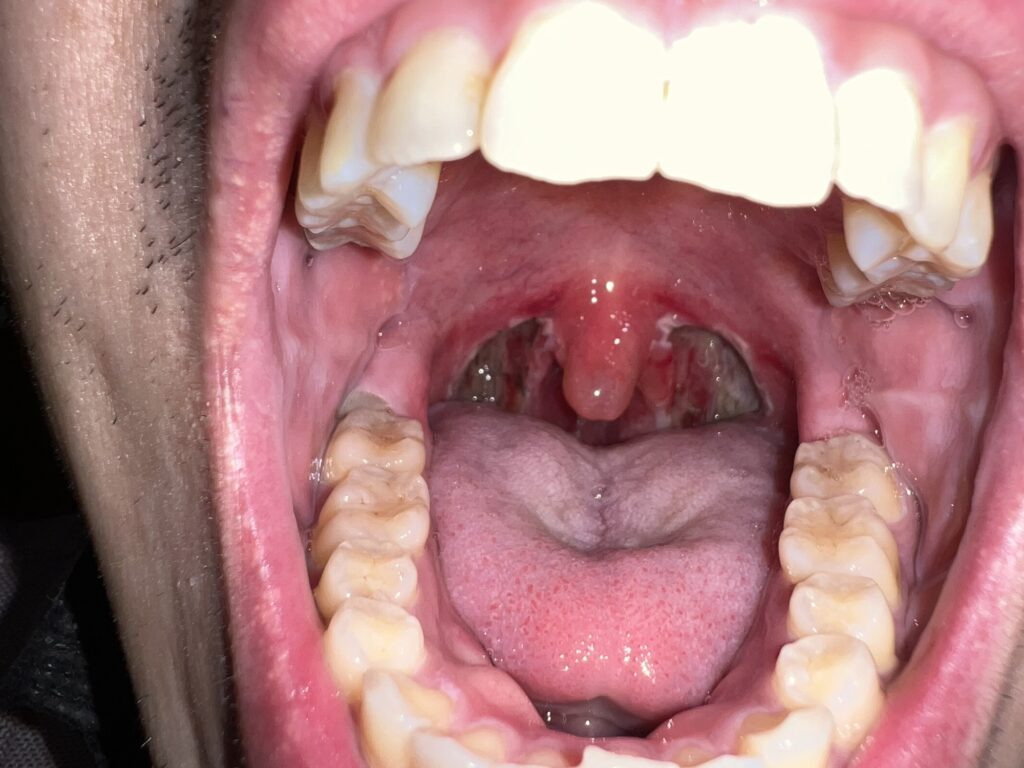

11月17日(手術前)

手術前夜に記念にとパシャリ。中学校2年生の時から共に過ごしてきたポリープちゃんの見納めです。さようなら。